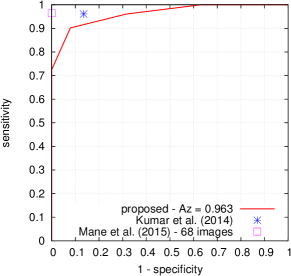

FROC curves are reported in Fig. 6 for ‘net B’; areas under the limited FROC curve for all three ConvNets are summarized in Table 3. It appears that the number of false alarms is rather large, particularly in the case of microaneurysm detection. The reason is that human experts primarily segmented the most obvious lesions, while screening algorithms need to focus on the most subtle lesions as well. In other words, many true lesions are counted as false alarms. Of course, this comment also applies to competing automatic solutions. To show the value of our detections, the proposed solution was compared in Fig. 7 to results reported in the literature, following the DiaretDB1 standardized procedure (see section 5.3.2). Most authors reported a single (sensitivity, specificity) pair: this is what we reported in Fig. 7. Some authors reported ROC curves; in that case, we also reported a single (sensitivity, specificity) pair: the one closest to the (sensitivity = 1, specificity = 1) coordinate. Note that all competing solutions (Kauppi et al., 2007; Yang et al., 2013; Franklin and Rajan, 2014; Kumar et al., 2014; Bharali et al., 2015; Mane et al., 2015; Dai et al., 2016) are trained at the lesion level, while ours is trained (in Kaggle-train) at the image level.

Three ConvNets were trained to detect referable DR in the Kaggle-train dataset, using the proposed heatmap optimization procedure. Then, we evaluated how well those ConvNets could detect lesions in the DiaretDB1 dataset, without retraining them. For lesion detection at the image level, they outperformed previous algorithms, which were explicitly trained to detect the target lesions, with pixel-level supervision (see Fig. 7). This superiority was observed for all lesions or groups of lesions, with the exception of ‘red lesions’. Experiments were also performed at the lesion level: for all lesion types, the proposed algorithm was found to outperform recent heatmap generation algorithms (see Table 3). As illustrated in two examples (see Fig. 9 and 10), the produced heatmaps are of very good quality. In particular, the false alarms detected on the vessels, in the vicinity of true lesions in the unoptimized heatmaps ( maps), are strongly reduced with sparsity maximization (, , ). These experiments validate the relevance of image-level supervision for lesion detectors, but stress the need to optimize the heatmaps, as proposed in this paper. Note that detection performance is not affected much by image quality: very good detections are produced in the blurry image obtained with a low-cost, handheld retinograph (see Fig. 10). This is a very important feature, which opens the way to automated mobile screening. However, it can be observed that the ‘AlexNet’ architecture, which achieves moderate DR detection results, also achieves poor detection results at the lesion level, even after heatmap optimization (see Table 3): to ensure good detection performance at the lesion level, the proposed optimization framework should be applied to ConvNet architectures that achieve good image-level performance.